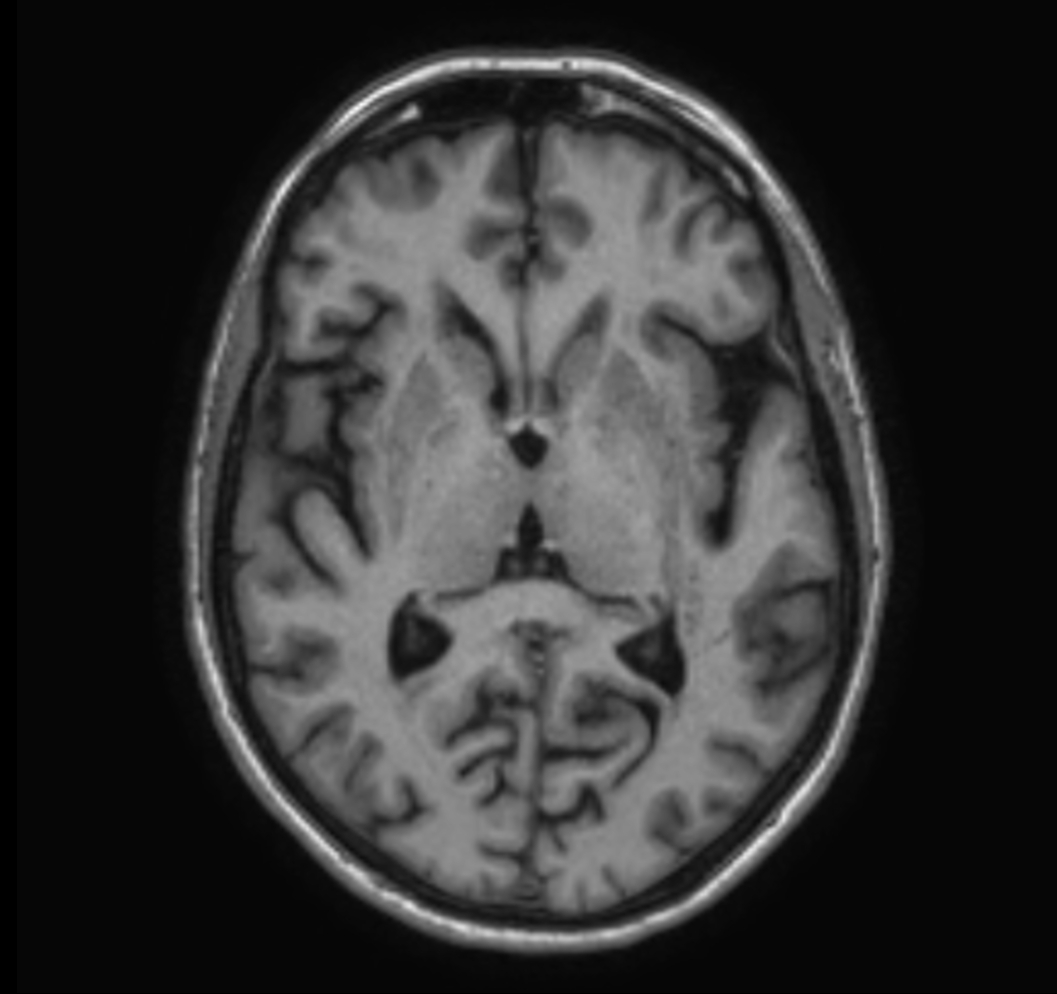

Sagittal 3D VIEW - T1w TFE